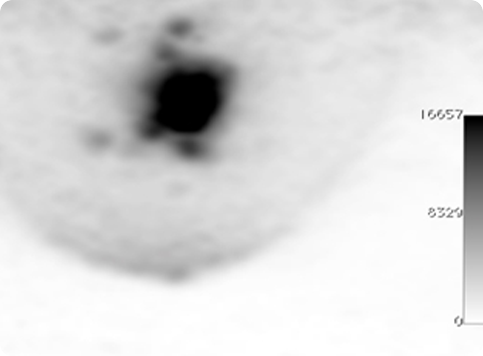

Figure 8

Measurement of DoI resolution in the ClearPEM scanner. The DoI resolution is 2.8 mm (FWHM).

Clear-PEM double readout scheme allows calculation of photon Depth of Interaction (DOI) and compensates blurring due to the parallax effect in PET resulting in an isotropic image resolution of 1.3 mm FWHM.